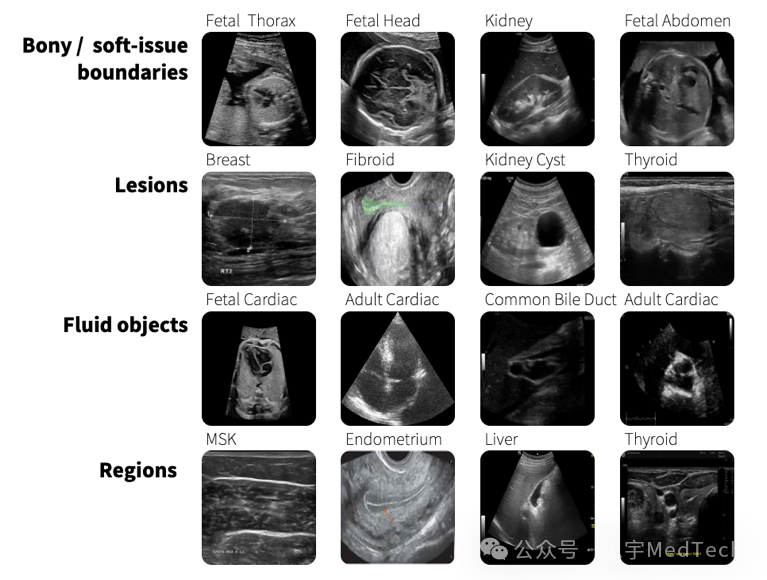

SonoSAMTrack结合了一个可推广的基础模型,用于分割超声波图像上的对象,称为SonoSAM。它可以分割超声波图像中的解剖结构,病变和其他重要区域。GE医疗还提供了一个名为SonoSAMLite的简化版本。

最近的一项研究表明,SonoSAMTrack在七个超声波数据集中表现出高性能。这些包括广泛的解剖学(成人心脏和胎头)和病理学(乳腺病变和肌肉骨骼病理学)。它们还包括不同的扫描设备。

▲示例超声图像的显示区域